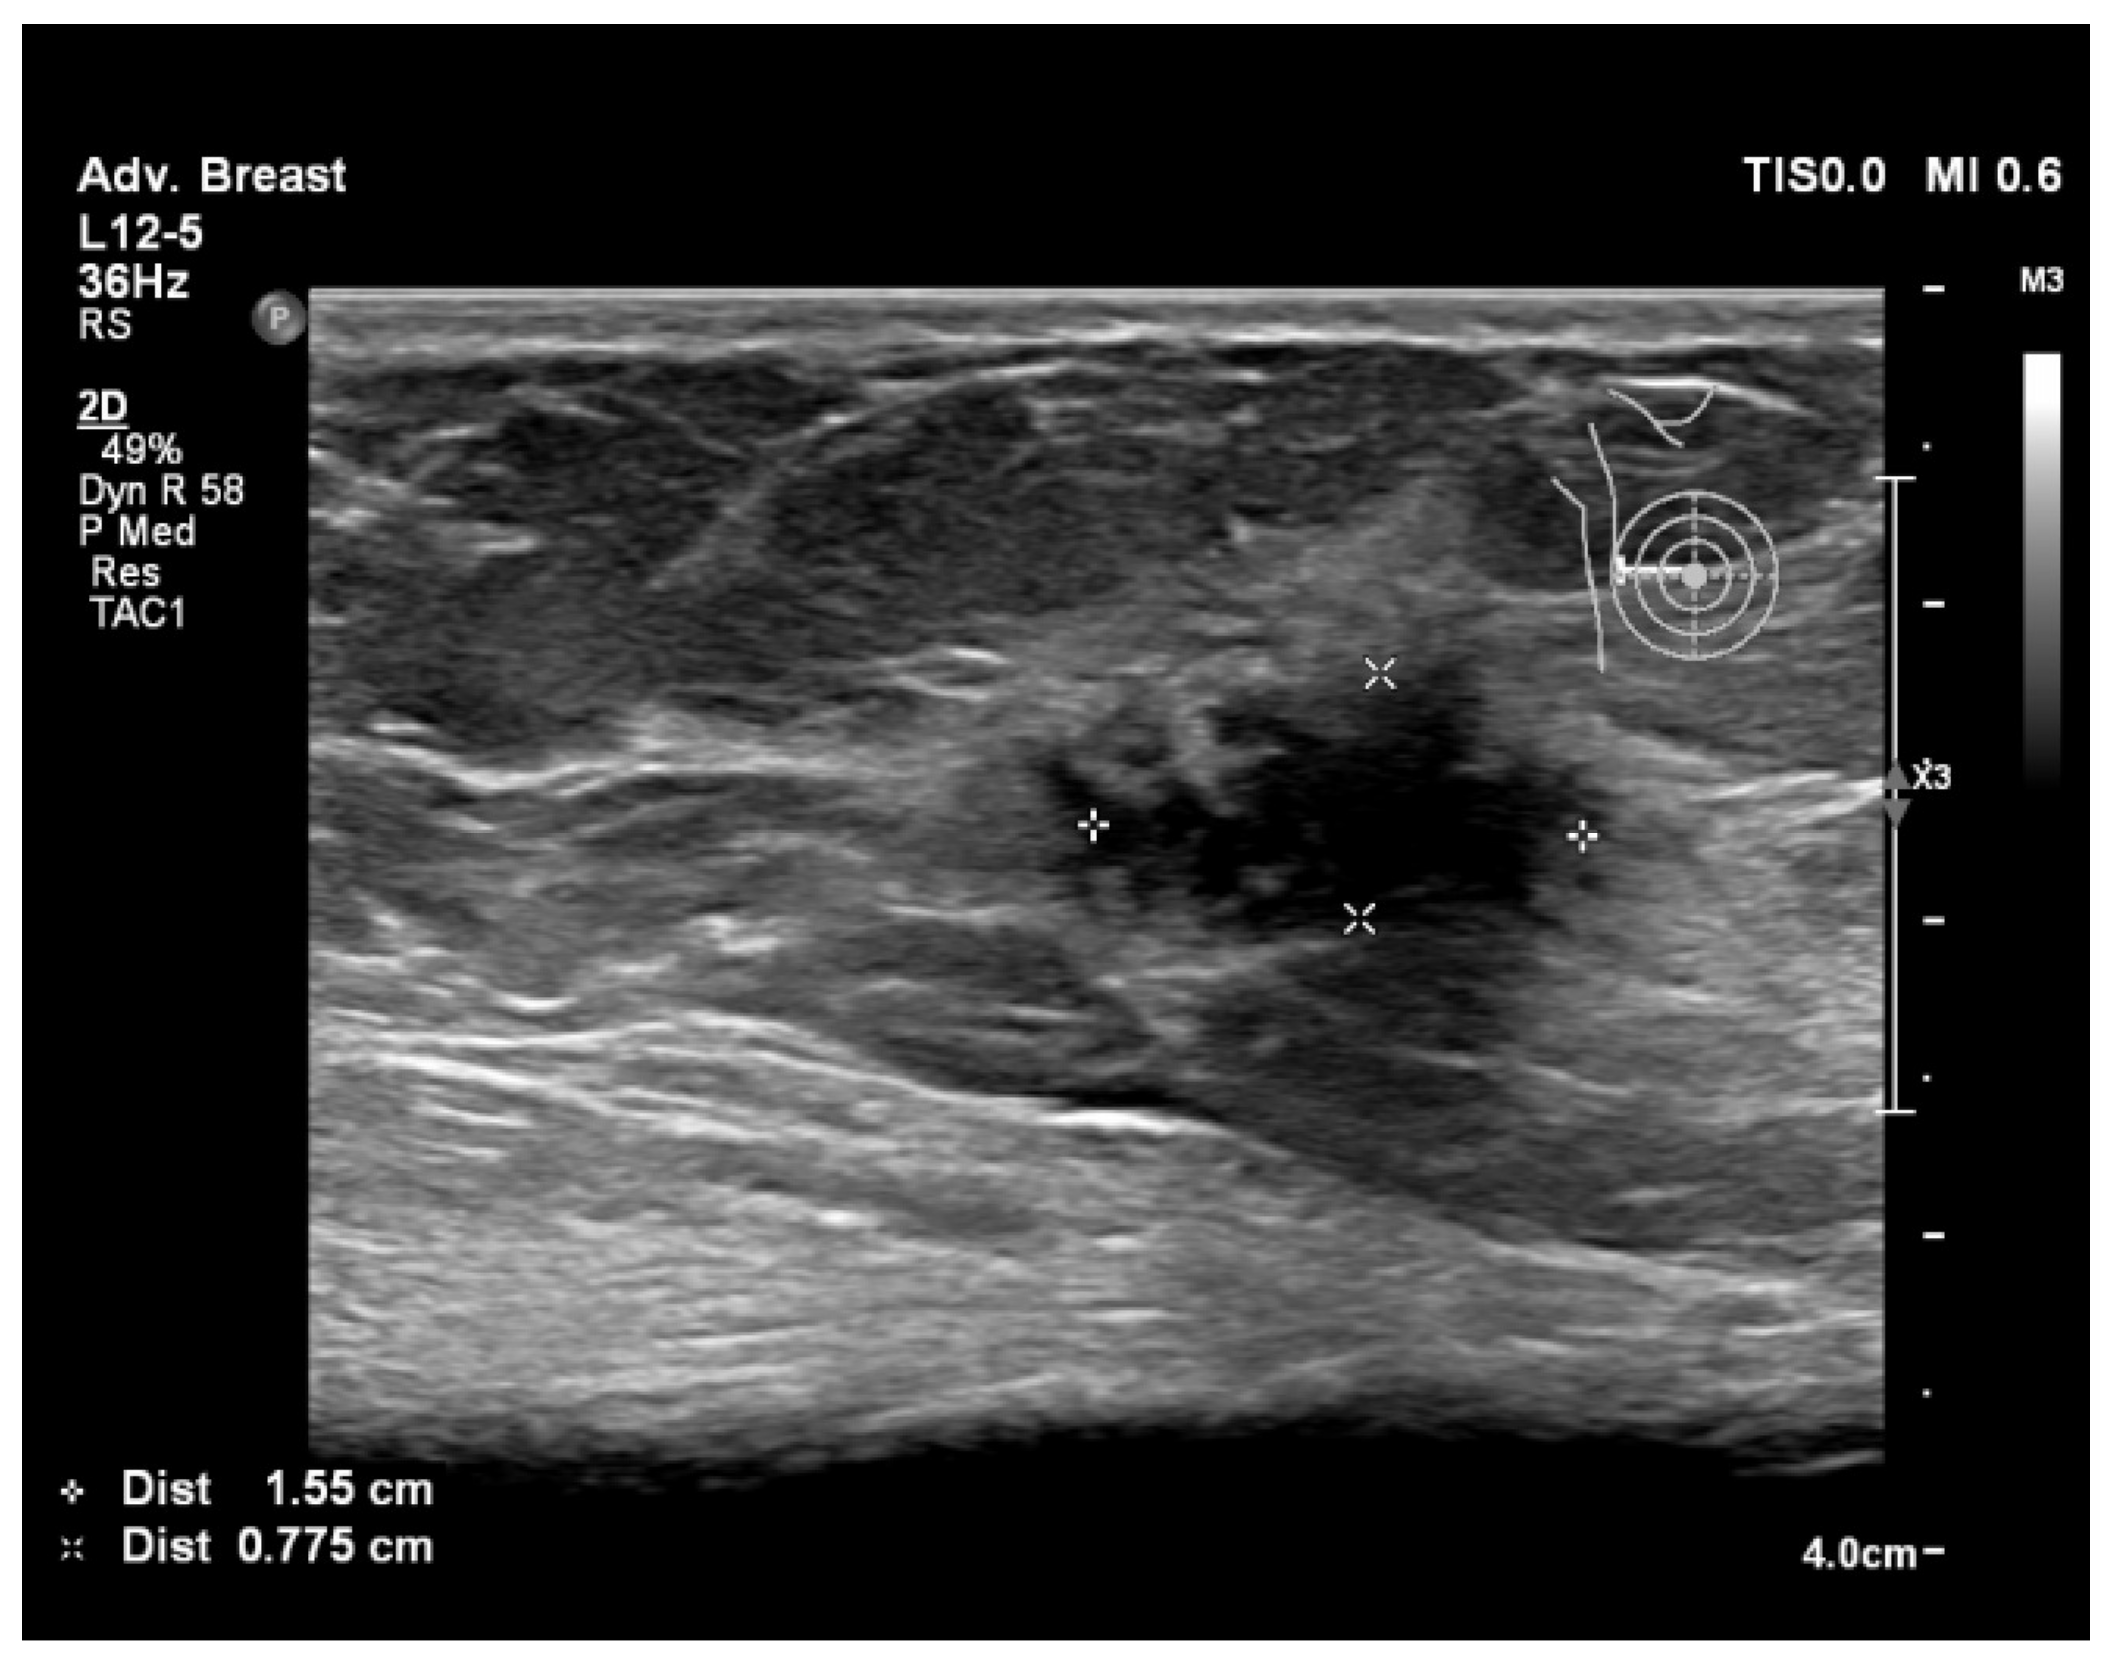

6.1. Characterization of Lesions

6.2. Real-Time Imaging and Guided Biopsies